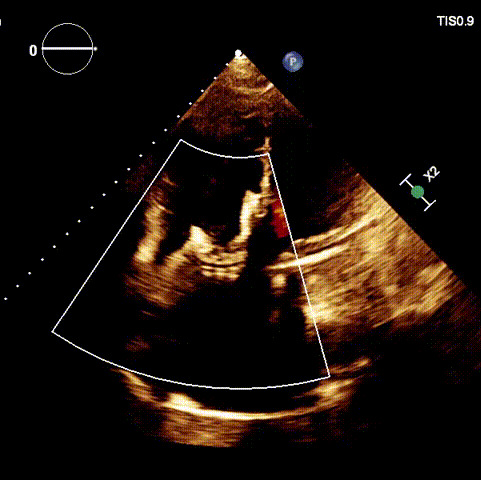

近日,廈門大學(xué)心血管病醫(yī)院王焱教授帶領(lǐng)的結(jié)構(gòu)性心臟病團(tuán)隊,成功應(yīng)用LuX-Valve Plus經(jīng)血管三尖瓣置換系統(tǒng),為一例高危三尖瓣重度反流患者開展經(jīng)血管三尖瓣置換手術(shù)。此次手術(shù)系LuX-Valve Plus人工瓣膜在福建省的首例植入,手術(shù)過程順利,術(shù)后患者三尖瓣反流顯著改善,標(biāo)志著由葛均波院士團(tuán)隊作為主要研究者的LuX-Valve Plus經(jīng)血管三尖瓣置換系統(tǒng)全國多中心臨床研究的再一次成功實踐,為三尖瓣介入治療的醫(yī)學(xué)循證打下了夯實的基礎(chǔ)。 、

術(shù)后超聲